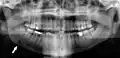

Минимально смещённый перелом правой нижней челюсти. Стрелка отмечает перелом, корневой канал на центральном резце, зубы слева от перелома не соприкасаются